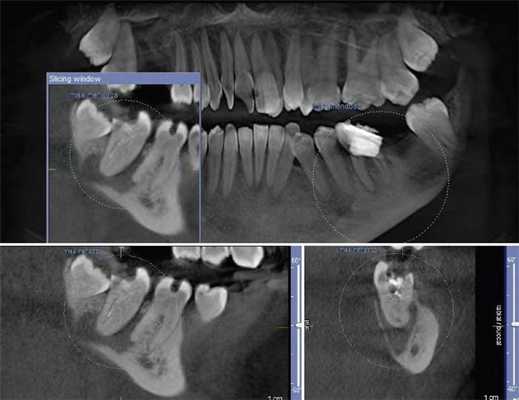

Выявлено, что у зубов с необтурированными КК при использовании распространенной в эндодонтической практике внутриротовой периапикальной рентгенографии, как правило, невозможно отчетливо визуализировать в каждом корне более 1 КК. В большинстве случаев это происходит из-за суммирования теней КК в каждом корне зуба (рис. 1, а; 2, а). В зоне нижней трети корней зубов отображение КК становилось нечетким либо вообще отсутствовало. При рентгенографии параллельной техникой изображение корней зубов было более качественным, чем при периапикальной съемке, но имело аналогичные закономерности (см. рис. 1, б). Использование для раздельной визуализации КК периапикальной рентгенографии в косой проекции приводило к ухудшению изображения нижних отделов корней всех групп зубов. На ОПМН КК зубов визуализировались недостаточно отчетливо (см. рис. 1, в).

Рис. 1. Исследование первого моляра верхней челюсти в эксперименте. При внутриротовой периапикальной рентгенографии (а), рентгенографии, выполненной параллельной техникой (б), в мезиальном щечном корне виден 1 КК; на фрагменте ОПМГ КК различаются нечетко (в); при КЛКТ на аксиальных срезах выявляются в мезиальном щечном корне 2 КК (г) и апикальные отверстия в дистальном щечном корне (д), на косом срезе определяется расположение корневых каналов (е).

Рис. 2. Исследование зуба 3.6. На внутриротовой периапикальной рентгенограмме (а) создается картина наличия только 1 канала в каждом из корней зуба; по данным аксиального среза КТ (б) отчетливо визуализируются по 2 КК в каждом из корней.

Рентгеновская КТ с построением аксиальных и косых срезов (см. рис. 1, г, д, е; 2, б) в сравнении с внутриротовой рентгенографией предоставляла объективные сведения о строении корней всех групп зубов. Информация о строении корней зубов, полученная при КТ перед эндодонтическими манипуляциями, позволяла заранее спланировать рациональную тактику лечения. В процессе эндодонтического лечения данные КТ способствовали сокращению времени на выявление устьев КК и повышению качества эндодонтического лечения.